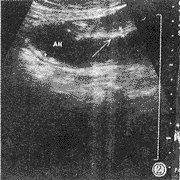

345例胃超声检查阳性患者108例,其结果显示如表1。浅表性胃炎、肥厚性胃炎典型表现如图2、图3所示。

图2 显示浅表性胃炎粘膜改变。